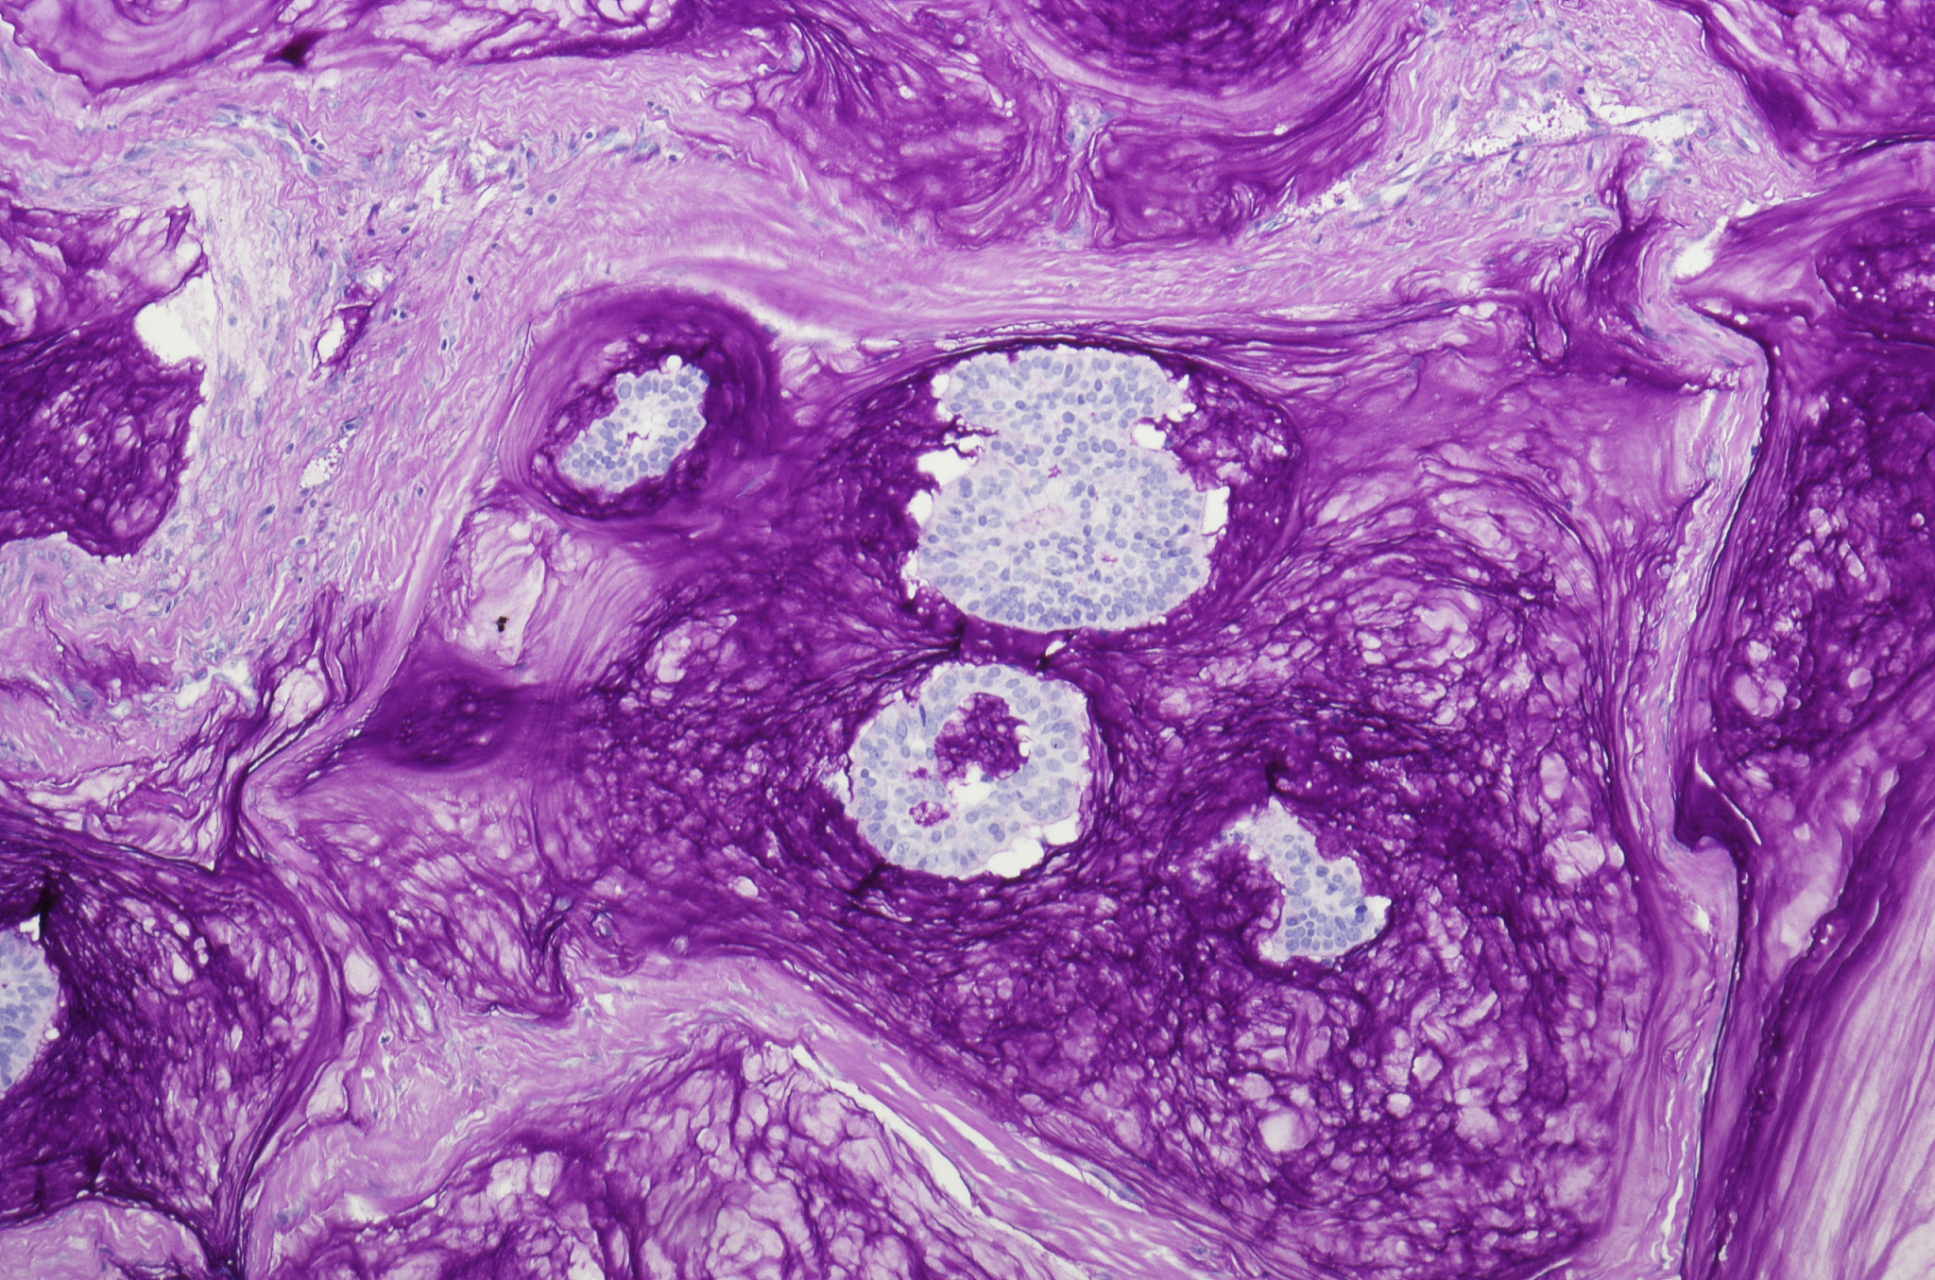

宫颈微小浸润性鳞状细胞癌

病理规培图库 || 宫颈微小浸润性鳞状细胞癌